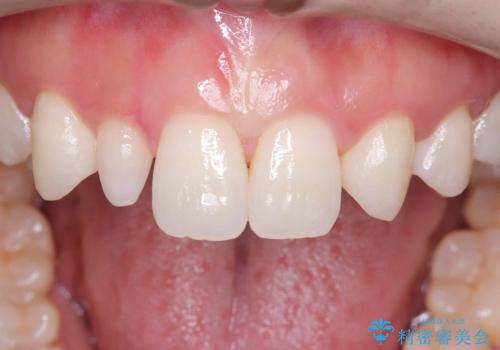

- 「前歯の見た目が気になる」を主訴に来院された患者様です。

右上2が矮小歯だったので、オールセラミッククラウンで審美修復しました。

- 税込165,000円(オールセラミッククラウンスペシャル154,000円+仮歯11,000円)費用は治療当時の料金となります